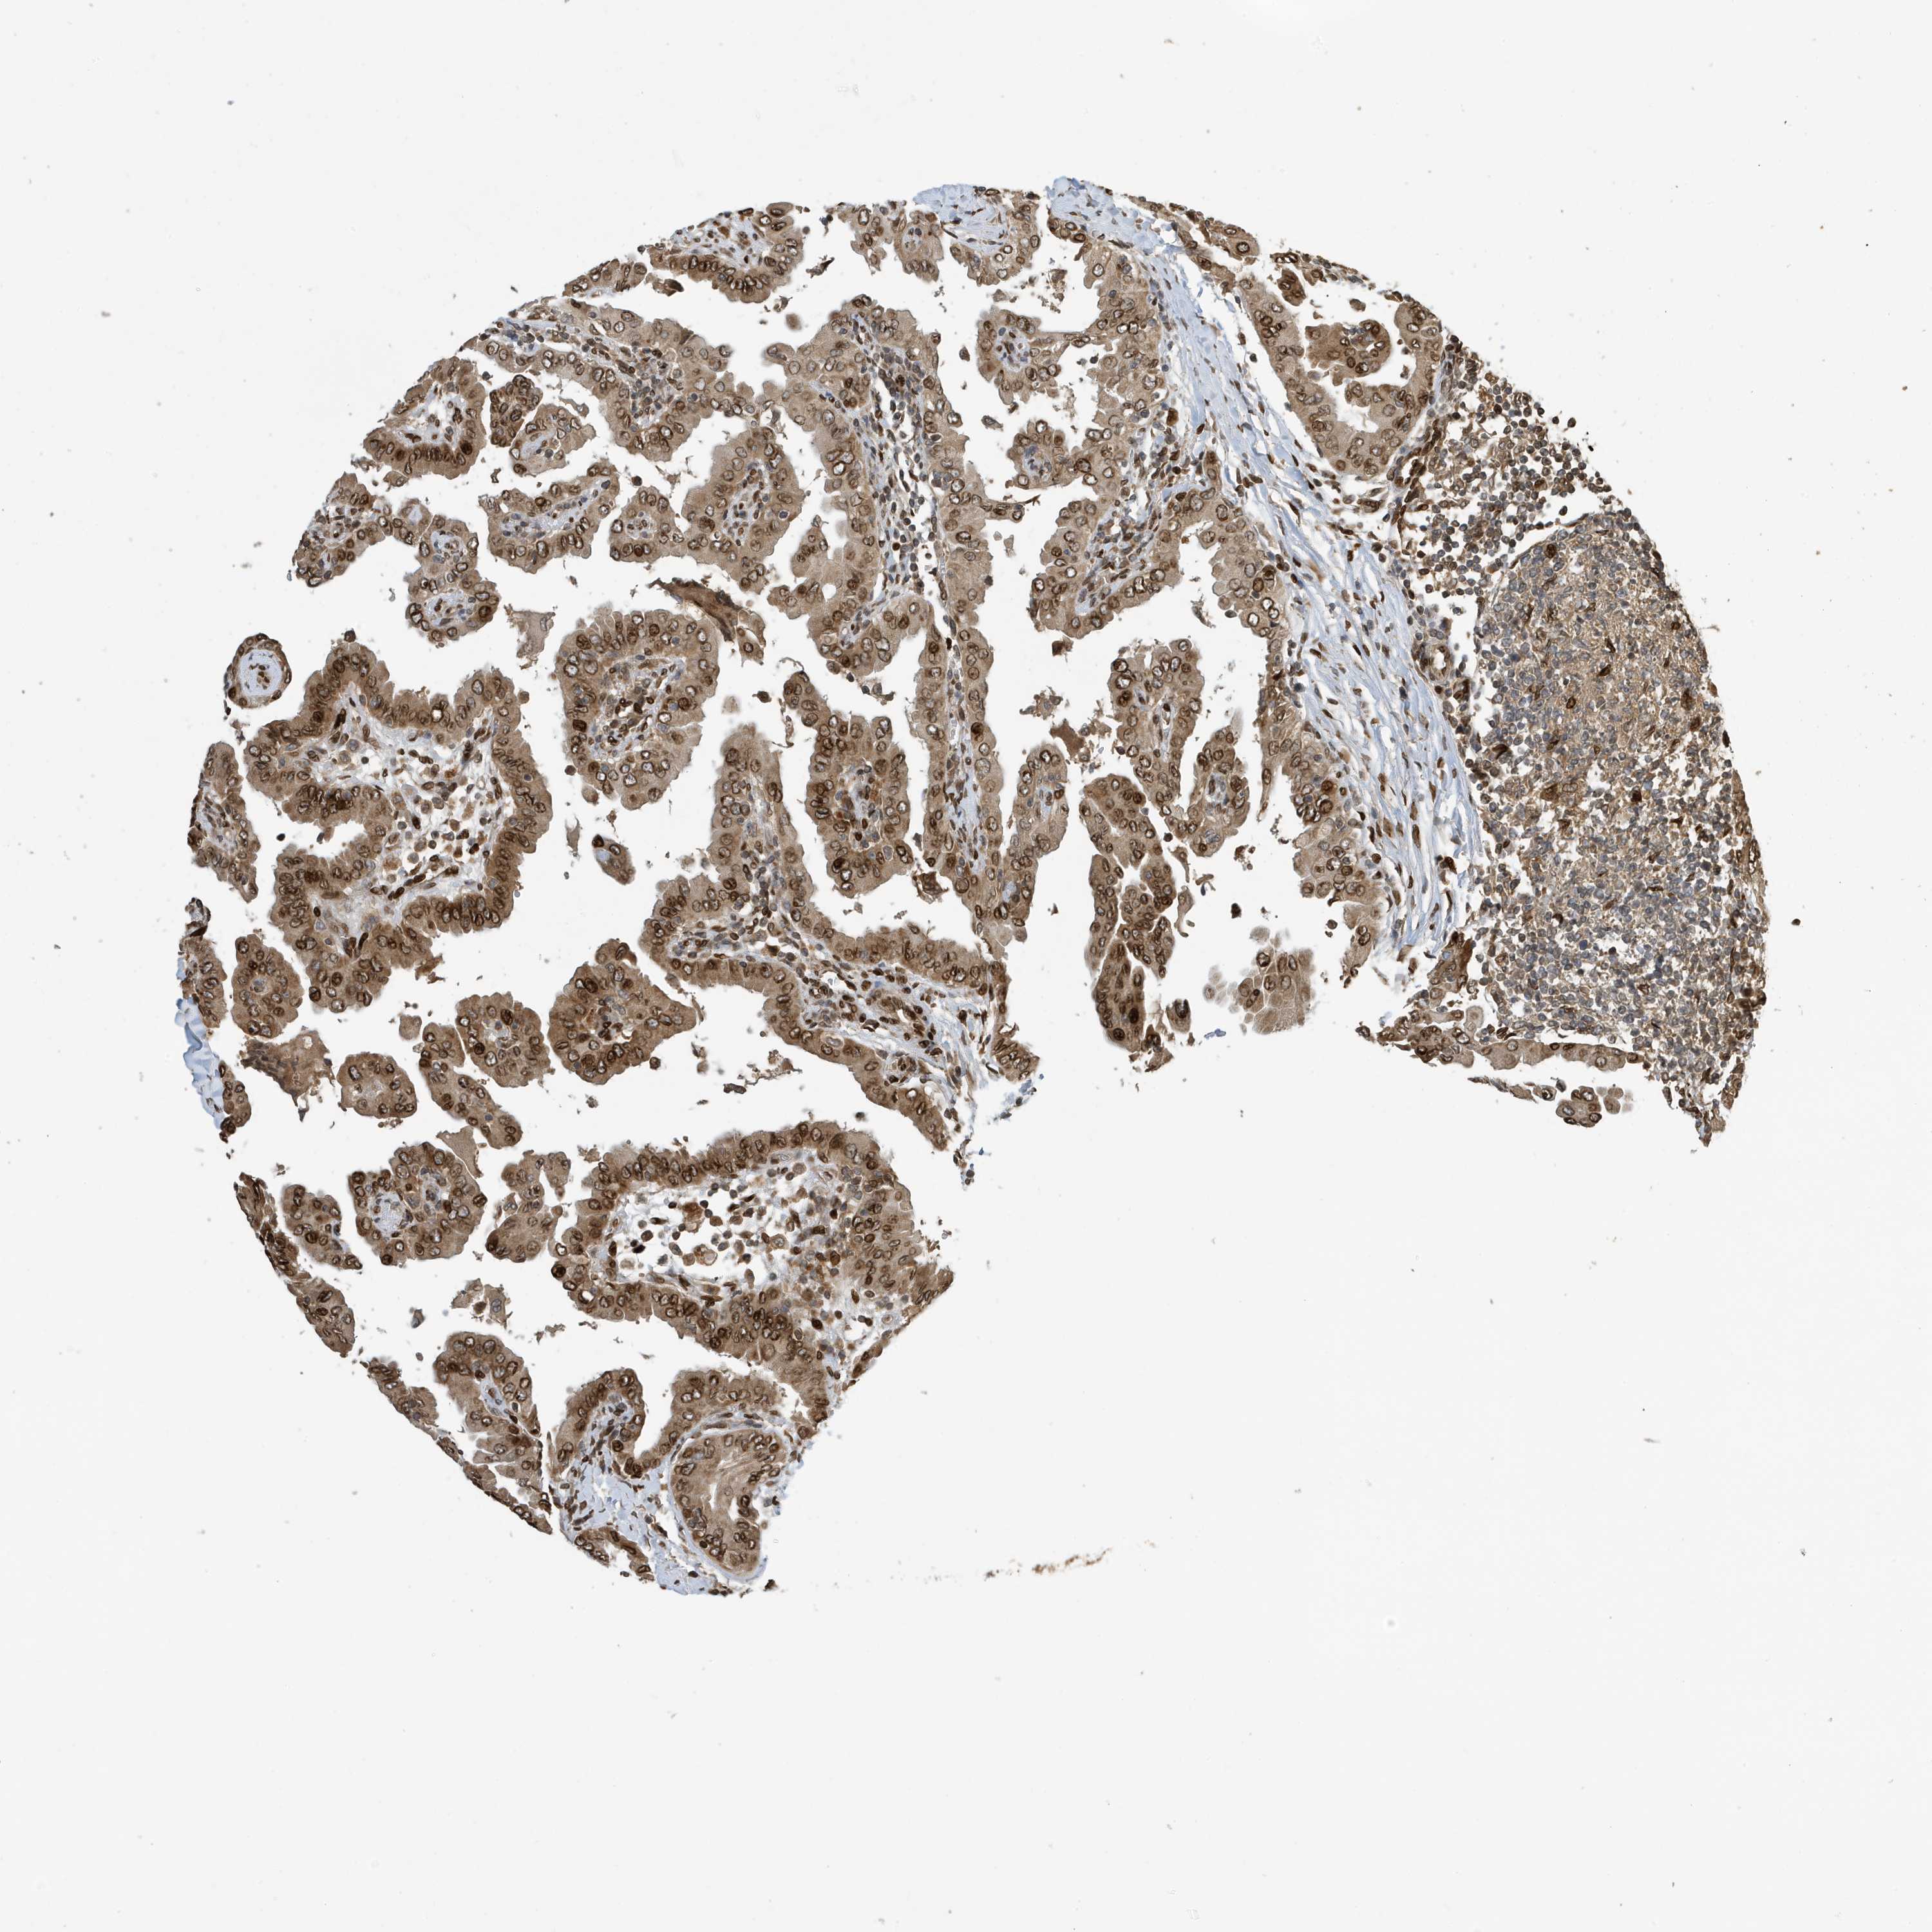

THYROID CANCER - Protein expressioni

A mouse-over function shows sample information and annotation data. Click on an image to view it in a full screen mode. Samples can be filtered based on level of antibody staining by selecting one or several of the following categories: high, medium, low and not detected. The assay and annotation is described here.

Note that samples used for immunohistochemistry by the Human Protein Atlas do not correspond to samples in the TCGA dataset.

Antibody stainingi

Antibody staining in the annotated cell types in the current human tissue is reported as not detected, low, medium, or high, based on conventional immunohistochemistry profiling in selected tissues. This score is based on the combination of the staining intensity and fraction of stained cells.

Each image is clickable and will lead to virtual microscopy that enables deeper exploration of all samples and also displays staining intensity scores, fraction scores and subcellular localization as well as patient and tissue information for each sample.

Antibody CAB034070

Staining

High

Medium

Low

Not detected

Intensity

Strong

Moderate

Weak

Negative

Quantity

>75%

75%-25%

<25%

None

Location

Nuclear

Cytoplasmic/membranous

Cytoplasmic/membranous,nuclear

Papillary adenocarcinoma, NOS

Follicular adenoma carcinoma, NOS